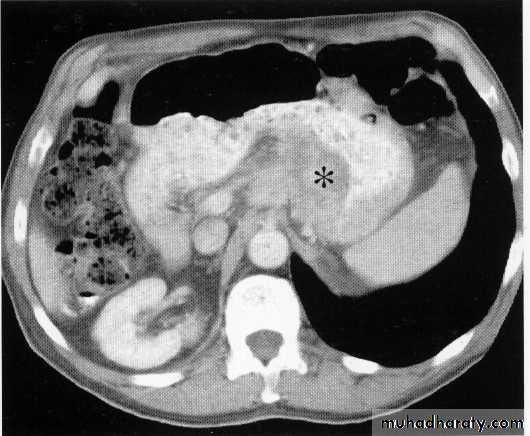

Liver abscess